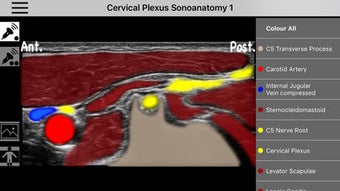

AnSo Anestesia Sonoanatomía es una aplicación para iPhone que proporciona una comprensión integral de la sonoanatomía relevante para el anestesista. Con más de 250 imágenes de ultrasonido y 1500 superposiciones de color de sonoanatomía, esta aplicación es un recurso conveniente diseñado para ayudar a los anestesistas a identificar la sonoanatomía común de manera eficiente en el tiempo dentro del ajetreado quirófano. Creado por anestesistas en ejercicio con interés en la enseñanza de la ecografía y la anestesia regional, AnSo proporciona múltiples ejemplos de la sonoanatomía ya que cada individuo es diferente.